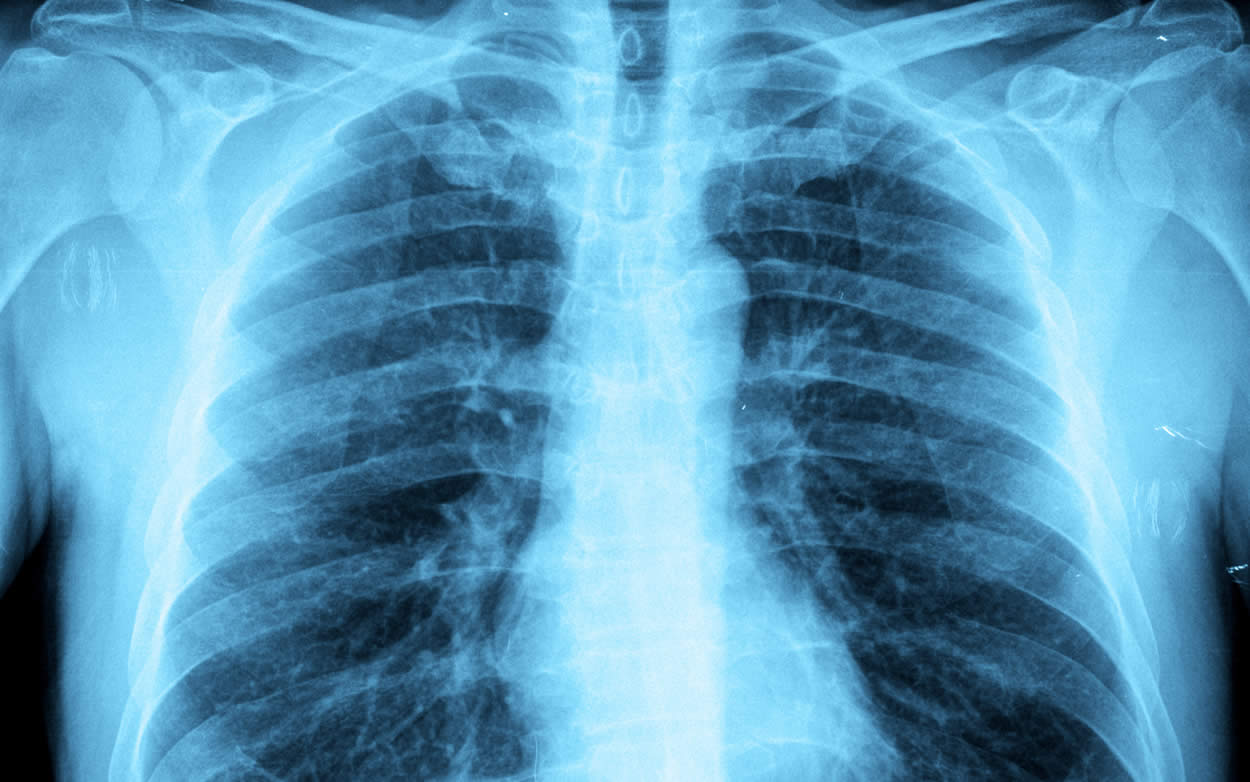

Los investigadores, con C. J. Cambier como autor principal, han informado de que el pulmón contiene una población de células inmunes especializadas, conocidas como macrófagos alveolares. Estas son la primera respuesta a las infecciones bacterianas, las cuales consiguen destruir en un 90% a la bacteria de la tuberculosis. Según los autores de esta investigación, esta es la razón por la que sólo entre el 5 y 10% de la población que padece tuberculosis lo desarrolla en su forma activa. Este hallazgo, supone “abrir el camino hacia nuevos enfoques terapéuticos para curar la tuberculosis ante la creciente alarma producida por el aumento de la resistencia antibiótica de los microorganismos”. Además, con estos resultados, los autores del estudio confían en identificar fármacos que permitan a estas células inmunes parar el camino de la infección, destruyendo a las micobacterias antes de que la enfermedad engañe al sistema inmunitario para que dañe nuestro propio tejido pulmonar y evitando así que se expanda la enfermedad a través de gotas de aerosol producidas en los episodios de tos.

Según los datos de la Organización Mundial de la Salud (OMS), la tuberculosis es una de las 10 principales causas de muerte en el mundo que afecta a una cuarta parte de la población mundial y causa la muerte de 5.000 personas cada día. A pesar de estos datos, sólo el 5% de esta poblacióndesarrolla este trastorno en su forma activa dentro de los primeros 2 años. La bacteria que causa la enfermedad es Mycobacterium tuberculosis, que en cuanto entra dentro del organismo a través de las vías respiratorias, provoca una reacción inflamatoria y es tragada por los macrófagos de los pulmones. Posteriormente, los macrófagos y otras células inmunitarias se acumulan en la zona infectada y forman un granuloma, que confina la bacteria y, en condiciones normales, impide que se extienda. Este acto se llama infección latente. En situaciones de inmunodeficiencia, el bacilo es capaz de reactivarse y provocar la enfermedad.